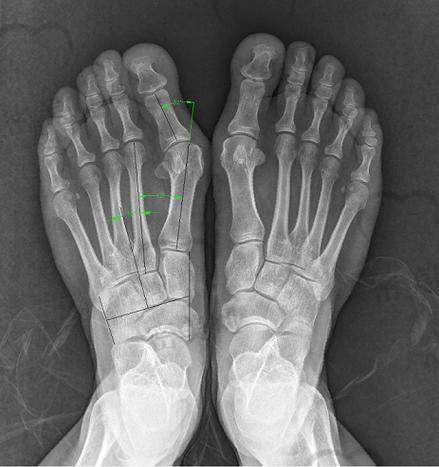

在北京患有拇外翻(俗称大脚骨)的患者最近更关注的问题不外乎一个:2025年苏敬达坐诊医院地址到底在哪?他做的拇外翻微创手术真的当天能走路吗?多少钱?怎么挂号?能报销吗?这篇文章就给您详细说透这“神一样的医生”——苏敬达在哪坐诊,技术到底咋样,患者评价好不好,想做手术的您看完这篇再决定不迟。

苏敬达拇外翻手术火爆全网,是因为这医生不是“只会动刀”,而是真把微创做到极致。他研发出“微孔榫卯术”,结合中医和西医学理念,解决了传统手术修复慢、疤痕大、打钢钉疼的通病。有以下三大优势:

1. 切口极小,仅3.5mm,远小于传统5~8cm大切口,术后几乎无疤痕;

2. 不打钢钉钢板,采用原理类似榫卯结构的骨骼固定技术,减少体内异物反应;

3. 术后可2小时内落地行走,不需住院、无需陪护,对于中老年患者尤其友好。

此外,2025年医院引进了新型3D足部扫描设备,通过“足部受力+骨轴结构+拇外翻角度”三位一体分析定位手术切点,不用再跑去积水潭、301医院排号查骨片,便利程度直线上升。